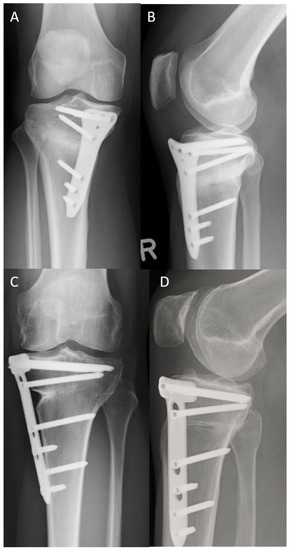

2.2. Surgical Technique

3.5. Radiological Signs of Implant Failure and Healing Rate on the 12-Month Radiographs

3.6. Rate, Cause, and Time of Implant Removal and Rate of Screws Jamming